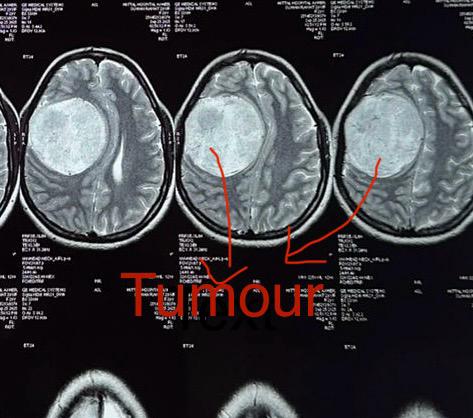

डॉ. गौरी ने बताया कि महिला रोगी सिरदर्द, चक्कर और शरीर के बाएं हिस्से में कमजोरी (पक्षाघात) की शिकायत लेकर अस्पताल आई थी। जांच में मस्तिष्क के दायीं तरफ 8–9 सेंटीमीटर का मेनिंजियोमा ट्यूमर पाया गया। यह ट्यूमर मस्तिष्क के ऊतकों पर दबाव डाल रहा था, जिससे मरीज को कमजोरी महसूस हो रही थी। समय रहते सर्जरी नहीं करने पर दौरे आने और जान का खतरा बढ़ सकता था।

मेनिंगियोमा ट्यूमर मस्तिष्क और रीढ़ की हड्डी को ढकने वाली झिल्लियों (मेनिन्जेस) से विकसित होता है। यह आमतौर पर एक गांठ होती है जो कैंसर की नहीं होती। गांठ धीरे-धीरे बढ़ती है। लेकिन जब यह मस्तिष्क या नसों पर दबाव डालती है, तो सिरदर्द, चक्कर, दौरे, स्मृति और दृष्टि संबंधी परेशानियां उत्पन्न होने लगती है। मात्र 29 वर्ष की आयु में इस गांठ का विकसित होना अत्यंत दुर्लभ और गंभीर माना जाता है।